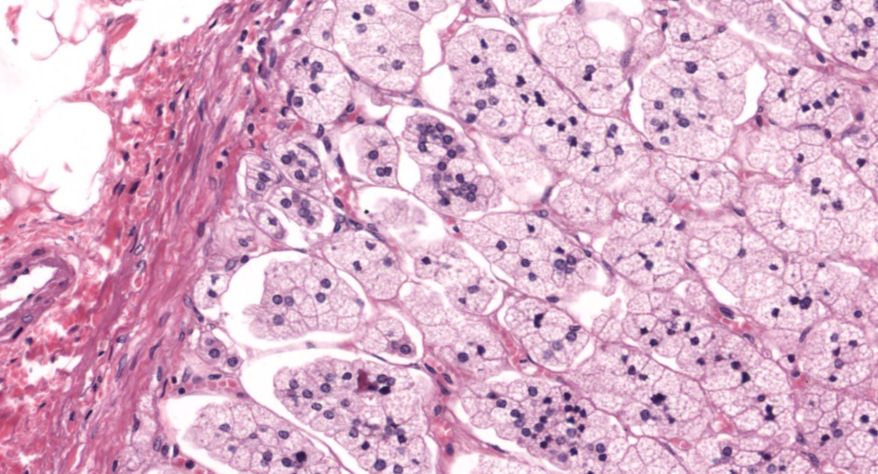

低倍镜观察:1. 被膜:由薄层结缔组织组成。2. 实质:由许多大小不等的滤泡构成。滤泡壁是单层立方上皮细胞,滤泡腔内充满粉红色匀质胶状物,滤泡之间的结缔组织内有丰富的血管。高倍镜观察:1. 滤泡:滤泡壁的单层滤泡上皮细胞一般呈低柱状或立方状,胞质着浅色,细胞核呈圆形。滤泡腔内充满了粉红色匀质胶质。2. 滤泡旁细胞:体积较大,呈圆形或椭圆形;细胞核较大,呈圆形,着色较浅,细胞质染色也较浅。细胞或嵌在滤泡壁上或成团分布于滤泡之间。3. 间质:由结缔组织组成。位于滤泡之间。其中含有丰富的毛细血管及三五成群的滤泡旁细胞。

4.胶质

5.滤泡旁细胞1

7.滤泡旁细胞2